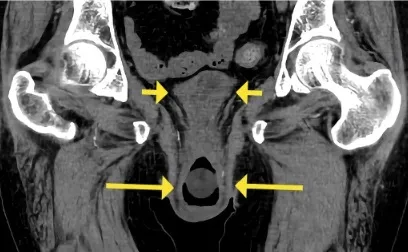

IRA + Icterícia: Um Caso que Exige Investigação Detalhada

IRA + Icterícia: Um Caso que Exige Investigação Detalhada